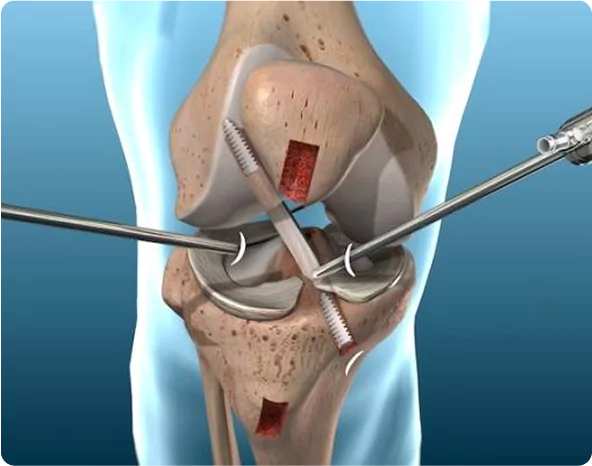

Revision knee replacement involves removing the old or problematic implant and replacing it with a new, highly stable prosthesis. This procedure is more detailed and technically demanding than primary knee replacement and requires an experienced surgeon skilled in managing infection, implant loosening, misalignment, and bone loss.

Revision knee surgery requires specialized implants, advanced surgical planning, and expert execution. Dr. Akash Saraogi uses the latest global techniques including computer-assisted alignment, bone reconstruction, revision-grade implants, and minimally invasive approaches when suitable.

✔ Correction of deformity or instability

✔ Restoration of bone loss using grafts or specialized implants